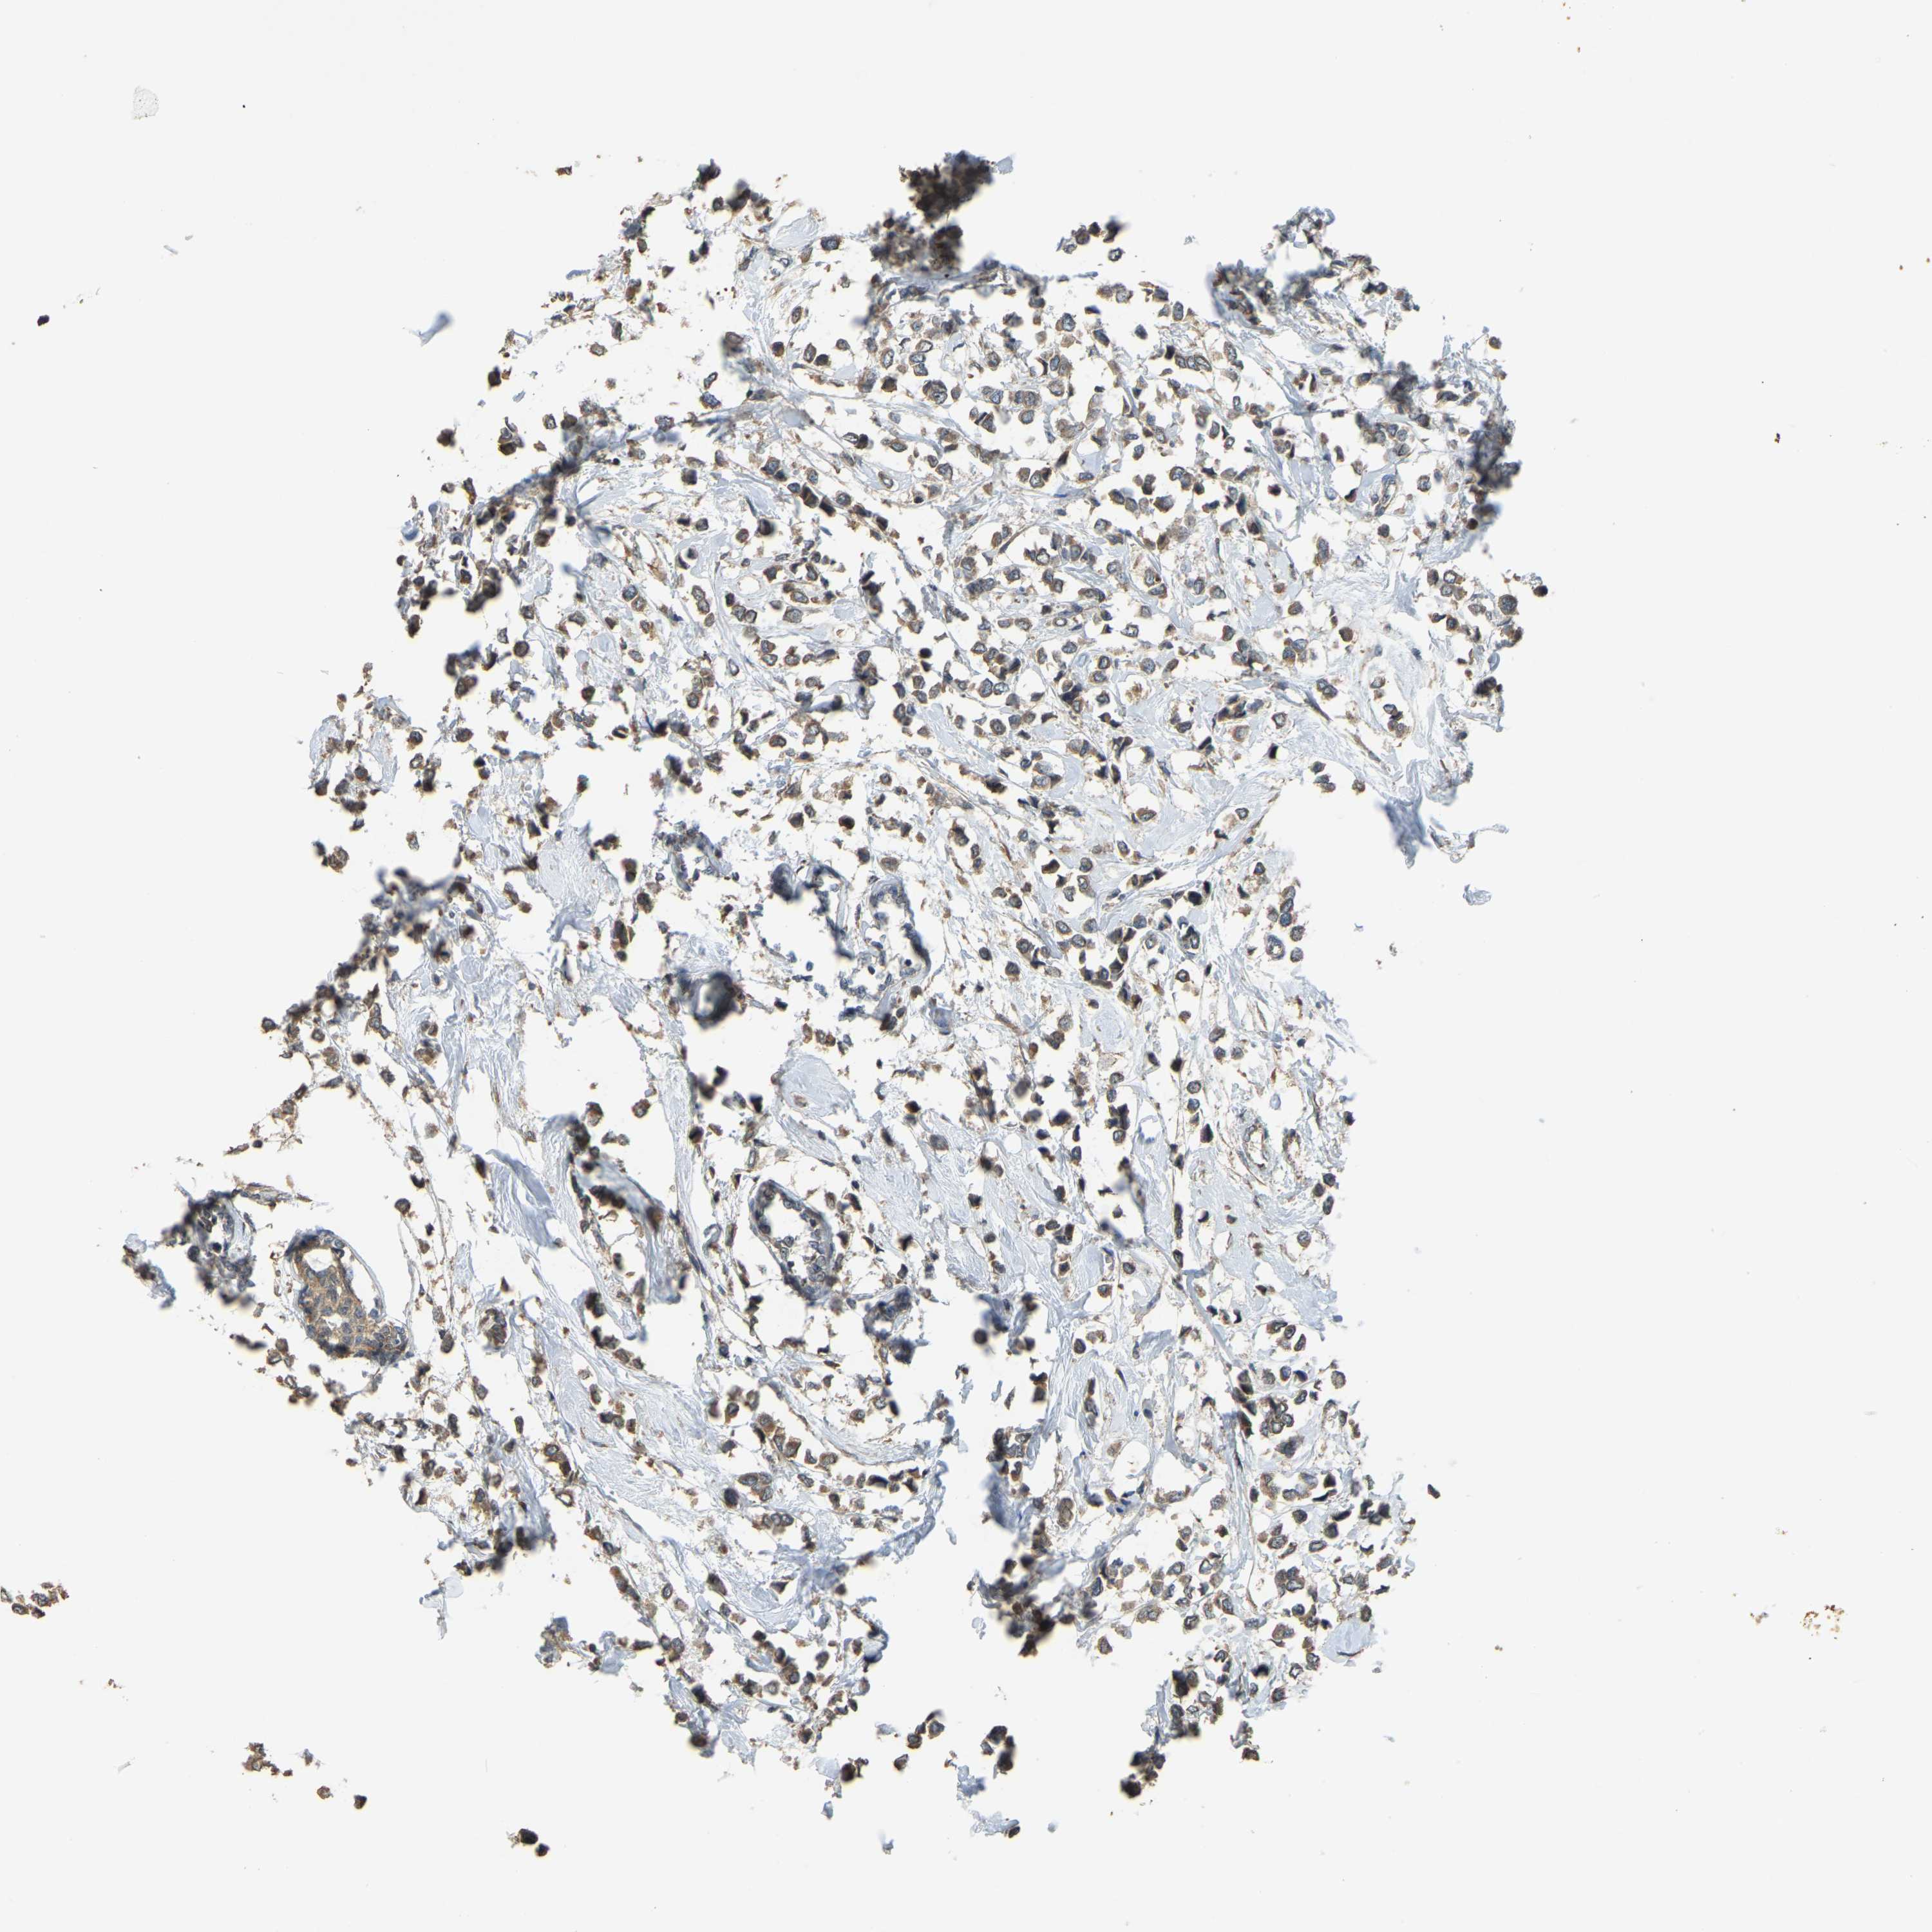

Breast cancer

Human cancer